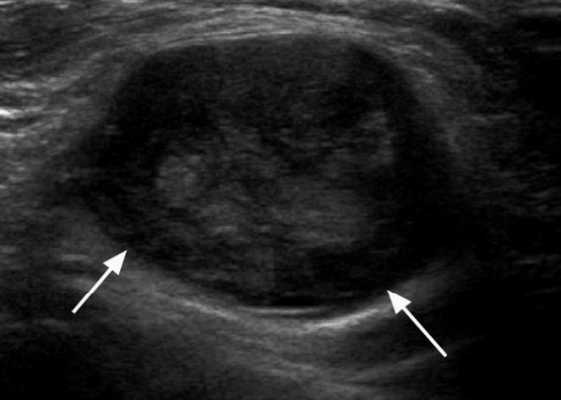

Практически во всех случаях дифференцировали лимфатический узел Кютнера (югулодигастральный), расположенный на границе средней и верхней трети шеи. Выявляемые лимфатические узлы имели размеры от 0,5 х 0,2 см до 2,3 х 0,8 см. УЗ-оценку производили после полипозиционного осмотра и нахождения самой длинной горизонтальной оси, что и принимали за максимальный поперечный диаметр. Большая часть лимфатических узлов (187) имели овальную форму с соотношением поперечного/переднезаднего более 1 (рис. 1 - 3). Тенденцию к округлению имели 30 лимфатических узлов, соотношение поперечного/переднезаднего приближалось к 1.

Мы установили, что, как правило, более округлая конфигурация лимфатического узла при его размерах, превышавших 10 мм, сопровождалась небольшими болевыми ощущениями, и более выраженной простудной (воспалительного характера) симптоматикой. Лимфатические узлы менее 10 мм чаще всего плохо пальпировались, либо вообще не выявлялись пальпаторно. Во всех случаях эхографически хорошо дифференцировался гипоэхогенный кортикальный слой и широкое, средней или чуть ниже средней эхогенности изображение области ворот лимфатических узлов. Четкость дифференциации составных частей лимфатического узла была снижена при размерах менее 5 мм. Мы отмечали различную толщину гипоэхогенного изображения области коры лимфатического узла: от очень широкой - при выраженности или прогрессировании воспалительного процесса, до узкой - на фоне положительной динамики.

Мы выявили совершенно другую УЗ-картину состояния пальпируемых лимфатических узлов при динамической оценке у больных с синдромом иммунодефицита. Оцениваемые лимфатические узлы имели эхографические признаки доброкачественного процесса, в большинстве наблюдений их размеры превышали 2-2,5 см. При этом во всех случаях дифференцировались составные части лимфатического узла. Определялся узкий кортикальный слой и широкая гиперэхогенная сердцевина при сохранении овальной конфигурации и соотношении поперечного/переднезаднего более 1.